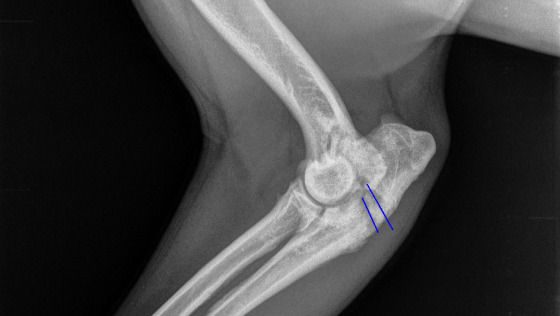

Zarówno artroskopia, jak i stabilizacja łokcia udały się doskonale, wszystko poszło gładko i bez komplikacji :)